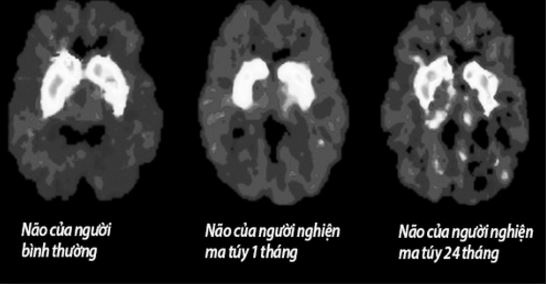

Mối liên quan giữa tổn thương não và sử dụng ma túy đá

Tổn thương não do sử dụng ma túy đá.

Các tác giả nghiên cứu này tiến hành dự án của họ, một phần, vì không có nhiều công việc đã được thực hiện để đánh giá mật độ các protein ở người hiện đang sử dụng methamphetamine hoặc ở người đang trong giai đoạn đầu cai methamphetamine. Dựa trên những phát hiện của mình, họ kết luận rằng người sử dụng methamphetamine mãn tính có thể phát triển sự gián đoạn đặc biệt nghiêm trọng trong việc sản xuất BDNF; sự gián đoạn protein này có thể dẫn đến giảm sút khả năng bảo vệ tế bào thần kinh. Từ đó giúp giải thích các tổn thương não liên quan với sử methamphetamine mạn tính. Tác giả nghiên cứu lưu ý rằng những thí nghiệm trong phòng thí nghiệm cho thấy mức độ BDNF bắt đầu tăng ở người sử dụng amphetamine sau khoảng 30 ngày ngưng amphetamine tuyệt đối. Các nhà khoa học trong tương lai cần phải xác định sự phục hồi tương tự xảy ra ở người đã ngưng sử dụng methamphetamine.